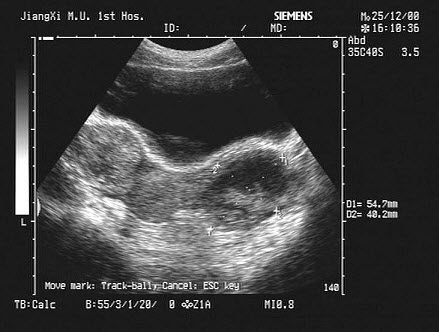

17、单项选择题

男,64岁,右上腹反复疼痛不适数10年,加重5天。声像图如图所示,诊断为()

A.肝内钙化带

B.胆囊充满型结石并萎缩性胆囊炎

C.胆囊蛔虫

D.肠襻回声

E.胆囊癌